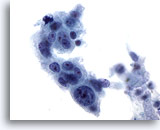

Figure 88

Bronchial wash

When in a cluster, it may be difficult to distinguish the cells of squamous cell carcinoma from adenocarcinoma. 20x

Bronchial wash

When in a cluster, it may be difficult to distinguish the cells of squamous cell carcinoma from adenocarcinoma. 20x

Figure 88

Bronchial wash

When in a cluster, it may be difficult to distinguish the cells of squamous cell carcinoma from adenocarcinoma.

20x

Bronchial wash

When in a cluster, it may be difficult to distinguish the cells of squamous cell carcinoma from adenocarcinoma.

20x